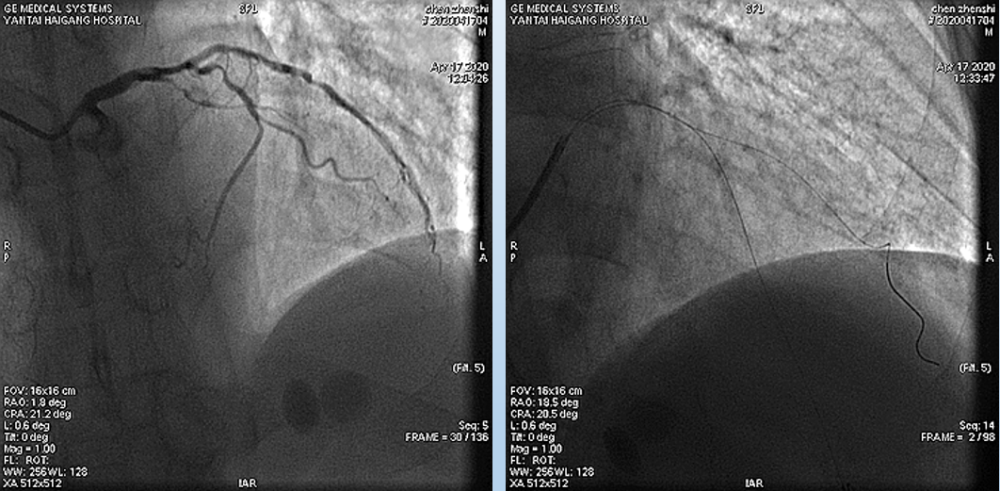

4月17日造影结果如图所示:

文章插图

冠状动脉供血为右优势型 , 冠状动脉开口正常 。 左主干未见明显狭窄;

前降支近中远段80%-99%弥漫性狭窄 , 前向血流TIMI 1级;

回旋支中段60%-70%弥漫性狭窄 , 远段可见50%弥漫性狭窄 , 前向血流TIMI3级;

右冠近中段80%-99%弥漫性狭窄 , 前向血流TIMI 2级

4月17日介入治疗结果如图所示:

根据造影结果及患者病情 , 决定优先处理前降支病变 , 择期处理右冠;

分别送导丝至前降支及第一对角支 , 送2.0mm×15mm预扩球囊对病变部位进行充分预扩张处理 。